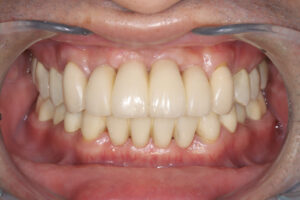

治療名

セラミック治療

費用

4,968,000円(税込み)

内:オールセラミック1本/120,000円、

治療期間

2年

通院頻度

1ヵ月 2~3回

治療結果

審美的な仕上がりで、患者自身も満足した。5年経過し良好である。

現在は2〜3ヶ月おきのメインテナンス中である。

治療を行う上での 注意点 (リスク・副作用)

オールセラミックには欠け易いといったリスクがあるためナイトガードは必須である。

特に清掃が重要である。